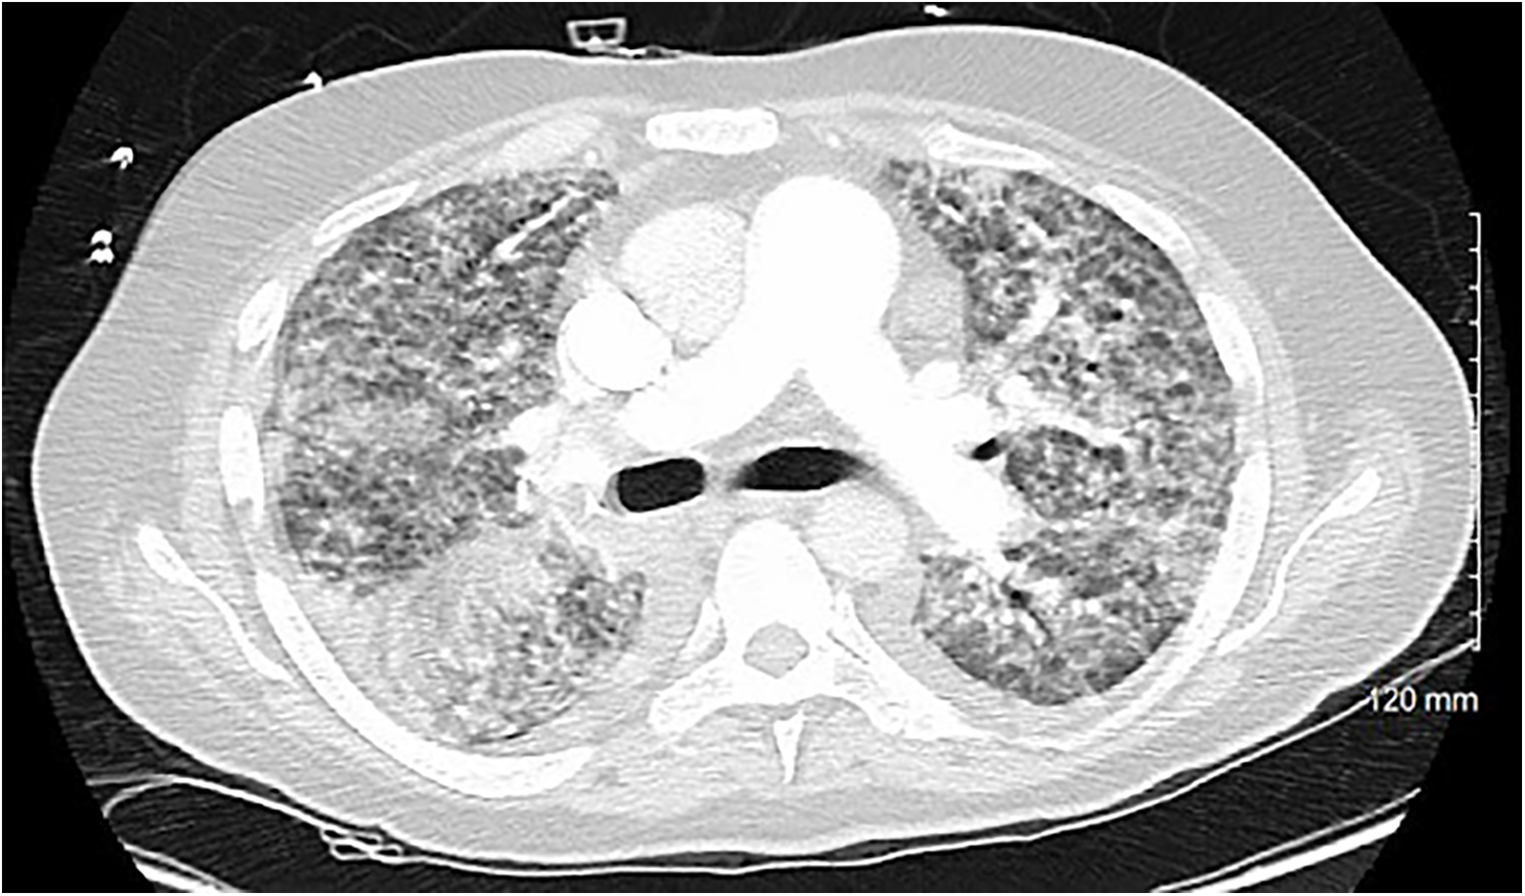

A 54-year-old otherwise healthy man presented to the emergency department with acute cardiogenic shock with respiratory failure (HR 124, SBP 120, RR 38, BNP 15,000) following a 10-day hospitalization 3 months’ earlier with COVID-19 pneumonia. The oxygen saturation rates were 68% on room air and 81% on 5 L of nasal cannula. He was also noted to have a lactic acid level elevated to 4. A computed tomography (CT) scan was performed, which showed diffuse pulmonary edema but ruled out pulmonary embolism (Figure 1). Due to respiratory decline, he was urgently intubated. A transthoracic echocardiogram was obtained, which showed severe mitral valve regurgitation with a flattening of the interventricular septum and a left ventricular ejection fraction of 70%. The mitral regurgitation was described as “severe” and the findings were consistent with endocarditis and papillary muscle rupture (Figure 2).

Figure 1

A cross-sectional CT scan performed upon arrival to the emergency department that rules out pulmonary embolism and shows bilateral interstitial consolidations consistent with pulmonary edema.